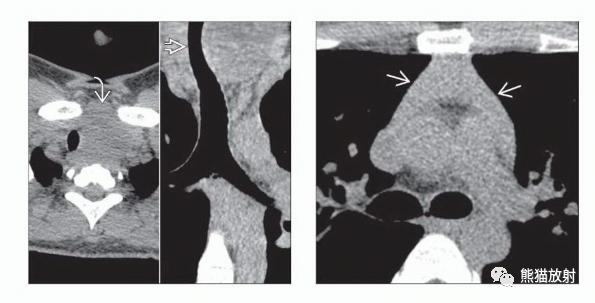

(左) 甲亢和淋巴组织胸腺增生患者的轴位和冠状位NECT图像显示甲状腺肿大,密度不均,对气管有占位效应。

(右) 同一患者,胸腺弥漫性增大,密度均匀,边缘轻度凸起。虽然大多数胸腺淋巴组织增生病例与重症肌无力有关,但其他自身免疫过程,如甲亢也与之有关。